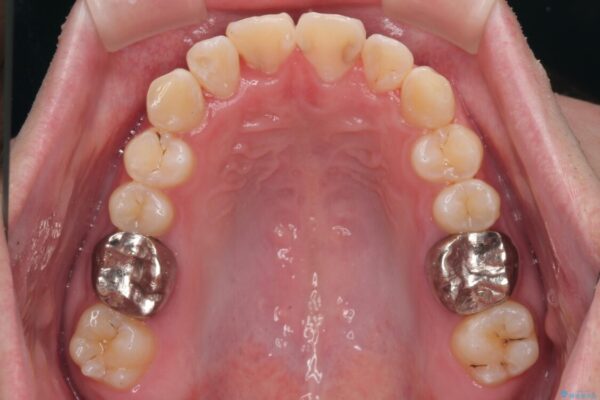

治療途中

• 1年でここまで変わる!歯列のがたつきと正中のズレを改善した矯正治療(メタルブラケット×MARPE) 治療途中画像

・特に上顎の幅が狭いため、下顎の歯列も内側に入り込み、歯が並ぶスペースが不足していました。

このような歯列の狭さに起因するデコボコを改善するために、**MARPE(骨に固定する上顎急速拡大装置)**を使用して、上顎の横幅を拡大し、これにより歯が並ぶためのスペースを確保し、メタルブラケットを用いて歯列を整えていく計画としました。